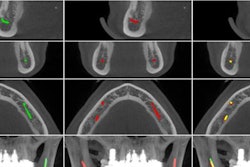

- More precise diagnostics: AI promises greater precision and accuracy in diagnostics. Dentists will be able to instantly tap into the wisdom of thousands of dentists from around the world with AI tools that have been trained to identify common pathologies from dental x-rays. Long-term, AI will deliver diagnostics that are exponentially more precise than any single dentist could possibly provide and serve as the new standard of care.